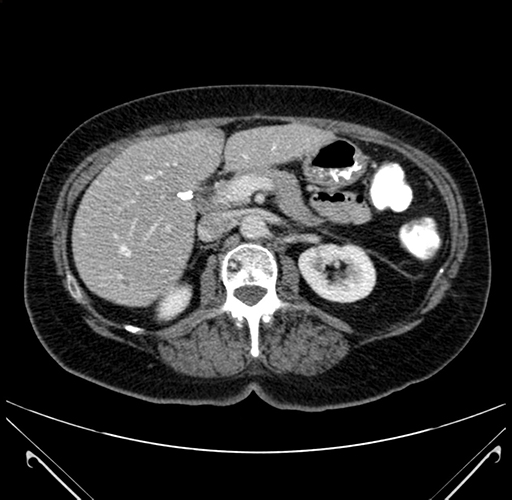

Pre-Chemo: Axial Venous